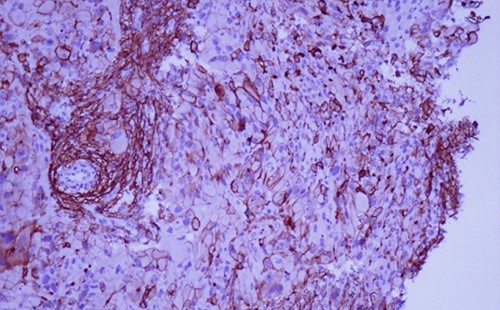

A 42-year-old man with no clinical history presented with a non-ulcerated polypoid skin nodule of the front side of the chest wall, which had grown over a period of 6 months, measuring 1,8 × 1,5 cm (Fig. 1). The lesion was removed completely with tumor-free margins of 0,5 cm. Microscopically, the tumor was composed of a diffuse infiltrate of polygonal cells with abundant granular cytoplasm and vesicular nuclei (Figs 2 and 3). There was no atypia or necrosis. The average mitotic count was one to two per 10 high-power field. Immunohistochemistry showed positive expression for CD10, CD68 and ALK with negative staining for CK AE1/AE3, CD34, S100 and HMB45 (Figs 4 and 5). No recurrence was noted during follow-up of 6 months.

Immunohistochemistry shows consistent negative expression of S100, smooth muscle actin, desmin, cytokeratin, CD34, HMB 45 and melan-A. CD10 and CD68 are usually positive [2, 3]. ALK antibody can be positive with weak to moderate cytoplasmic expression [6].

ALK gene fusion has been identified in some cases without significant chromosomal gains or losses or additional gene defects [6]. This funding is consistent with the good prognosis of these tumors.

Immunohistochemical staining for ALK is weak and focal (magnification at ×400).